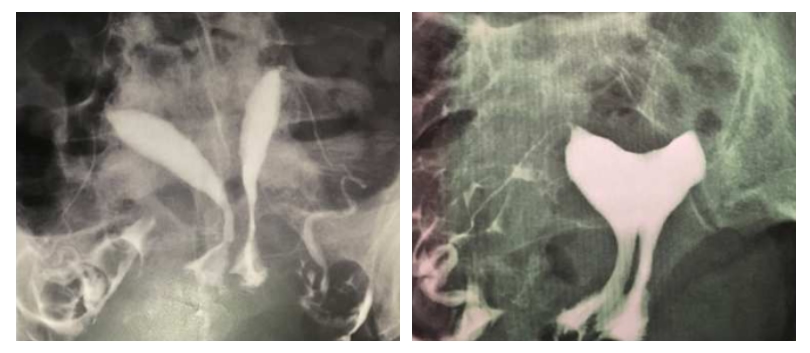

Another patient of mine is a 31-year-old woman who has had 2 miscarriages. She has a uterine septum and a vaginal septum. The pre- and post-operative images are as follows.